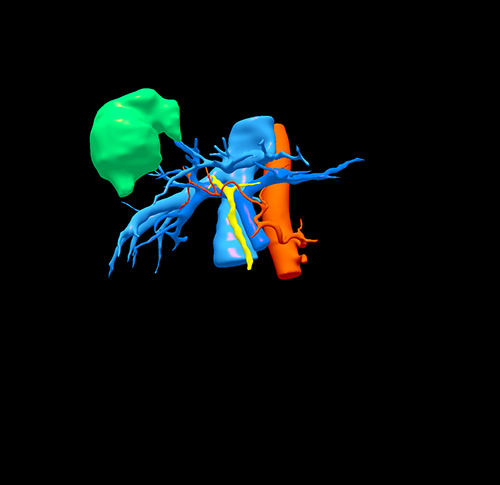

右肝肿瘤----腹腔镜右半肝切除